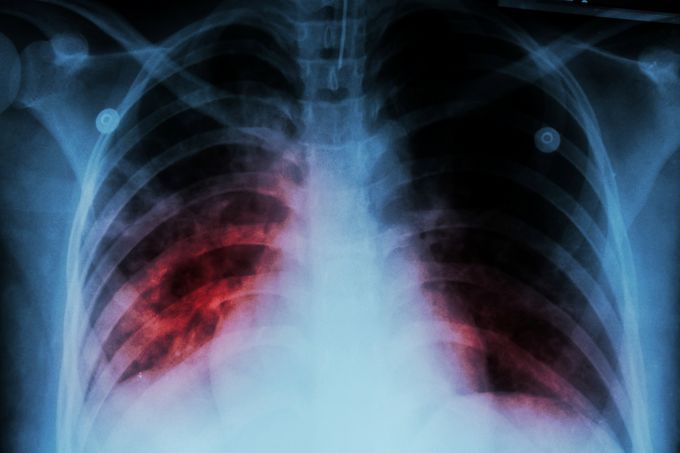

Tuberculosis (TB) remains one of the world’s deadliest infectious diseases. In 2024 alone, an estimated 10.7 million people fell ill with TB and 1.23 million died. Yet progress is possible: since 2000, global efforts have saved an estimated 83 million lives.